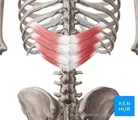

| Par images | Réponse | % Correct |

|---|---|---|

| dentelé postérieur inférieur | 16%

|

| dentelé postérieur supérieur | 16%

|

| transverses | 14%

|

| courts élévateurs des côtes | 11%

|

| longs élévateurs des côtes | 11%

|

| splénus | 7%

|